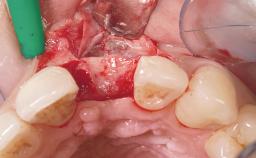

A 42-year-old female patient was referred to our clinic at the School of Dentistry of the University of São Paulo in November 2004, presenting a deficient restoration in the upper left central incisor. The clinical examination revealed no gingival retraction or any signs of gingival inflammation and, therefore, previous periodontal treatment was not considered. The patient presented a high lip line at full smile and a thin tissue biotype. This combination characterized a high-risk situation from an anatomic point of view, which required careful preoperative planning and cautious surgical execution.

Placement Protocol Immediate implant placement

Loading Protocol Immediate

Provisional Implant-Supported Prosthesis Prosthodontic margin < 3 mm apical to mucosal margin Prosthodontic margin < 3 mm apical to mucosal margin